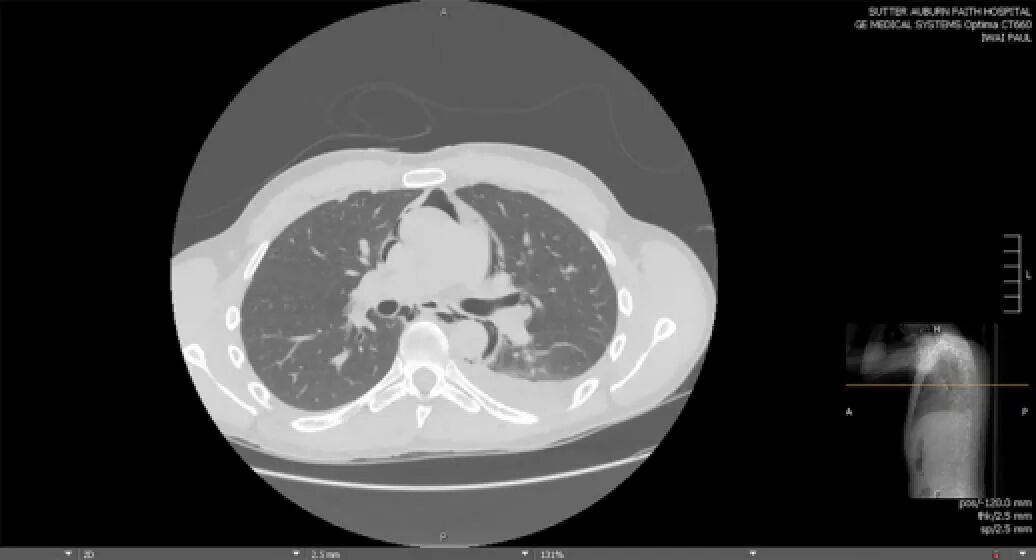

影像学检查:胸片示左肺底大片浸润影,伴有纵隔气肿和散在软组织内气体影,但无明显胸腔积液、气胸或肺水肿的征象。平扫CT检查(因肾功能不全未行增强CT)显示弥漫性纵隔气肿,气体延至双侧上胸部和颈部,伴左下肺实变影和双侧少量胸腔积液(如下图所示)。

图1 胸部CT示纵隔气肿和左侧胸腔积液